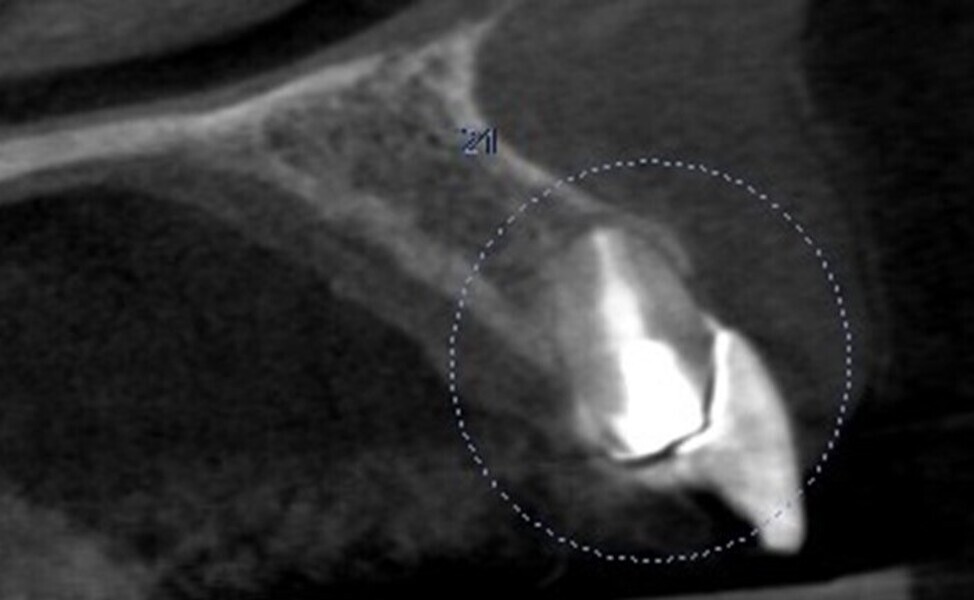

Fig. 4: Pre-op CBCT scan.